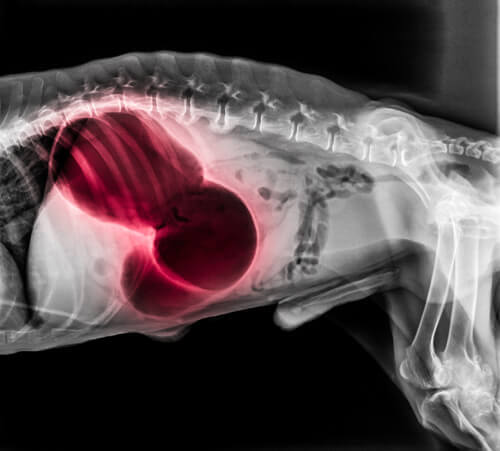

In their heart or lungs

A clot in the heart or the lungs could bring a variety of serious systemic symptoms, including fainting, shortness of breath and paralysis. Also, the dog’s gums might be pale or blue and they may not be able to sleep. And, they might also begin to cough up blood. Pulmonary thromboembolism is usually fatal.